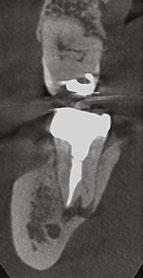

Figure 7: Planned-for access with the scan info on this extremely calcified canine Figures 8 and 9: 8. Deep distal split with PARL. 9. Missed buccal canal; history of previous RCT, post, crown and apico Figure 10: Retreatment consultation. PA from GD Figure 11: Scan images show a previously existing strip perforation

I’m also changing my treatment plans based on the data from my CBCT. Sometimes I look at a root canal treated PA and presume I know what I will do: a retreatment or an apico. Another recent, poignant case: a lower incisor with a previous RCT and a previous apico (Figure 9). Usually, once a tooth has had an apico, there may not be much left to offer and most of the time, the default is another apico, especially as there was very little room for an implant on the lower anteriors. I scanned the tooth and saw that a whole canal had been missed — twice! The RCT and the apico had left the buccal canal completely untouched. I changed my treatment plan based on this information!

Lastly, using CBCT also allows me to find issues that should be evaluated by another specialist. For example, when I capture incidental sinusitis, I can inform my patient to see an MD or ENT and can provide the 3D images to share with their physicians; or, to involve another dental specialist. (Figures 2, 4, 6, and 11 show incidental sinus findings.)